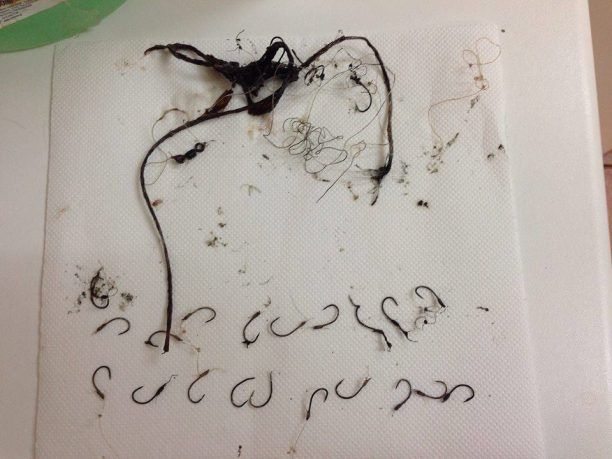

Η ακτινογραφία έδειξε τι είχε καταπιεί και πόσο βαθιά είχαν φτάσει τα αγκίστρια. Το Σάββατο 11 Οκτωβρίου οι ειδικοί άνοιξαν μια τομή στο λαιμό της καρέτα και έβγαλαν την πετονιά και τα 26 αγκίστρια. Τρία από αυτά όμως εξαιτίας του σημείου που έχουν αγκιστρωθεί έχουν μείνει στο σώμα του ζώου.

Στη χελώνα χορηγήθηκαν ειδικά λάδια που θα βοηθήσουν ώστε τα τρία εναπομείναντα αγκίστρια να ξεκολλήσουν και να απορριφθούν από το σώμα της εξήγησε στο www.zoosos.gr ο Γιάννης Ορφανός που ήταν ένας εξ αυτών οι οποίοι την εντόπισαν να κολυμπάει τυλιγμένη με τις πετονιές. Η καρέττα τώρα αναρρώνει στη μικρή πισίνα και θα μεταφερθεί στη μεγαλύτερη μόλις τις αφαιρέσουν τα ράμματα. Σε μερικούς μήνες θα κολυμπάει και πάλι ελεύθερη στην Αγία Άννα της Νάξου.